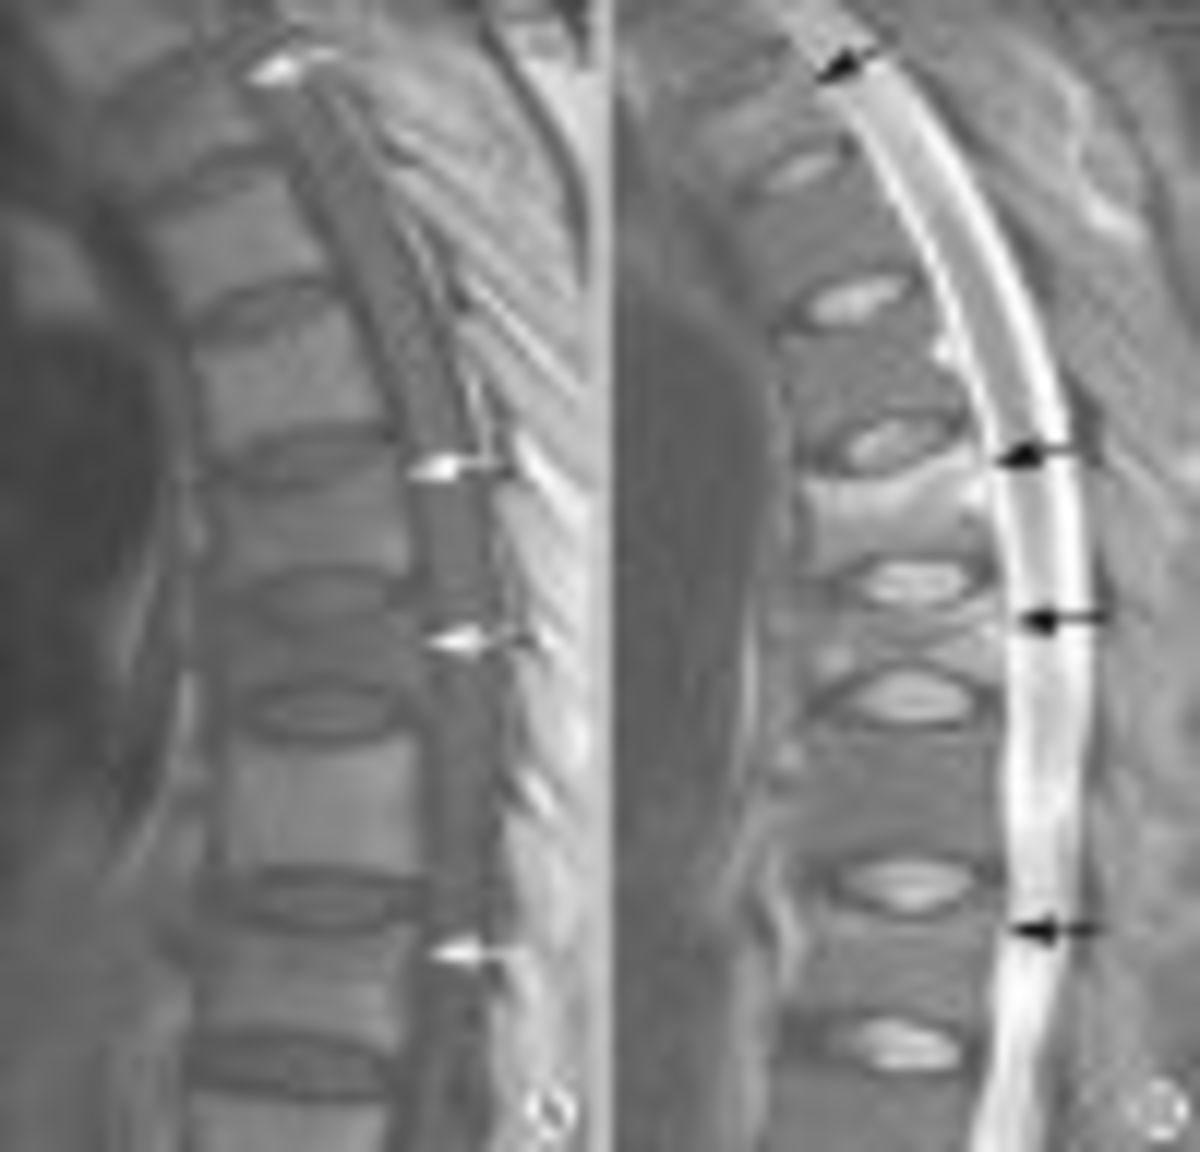

Oστεοπόρωση κατά την διάρκεια της κύησης και του θηλασμού